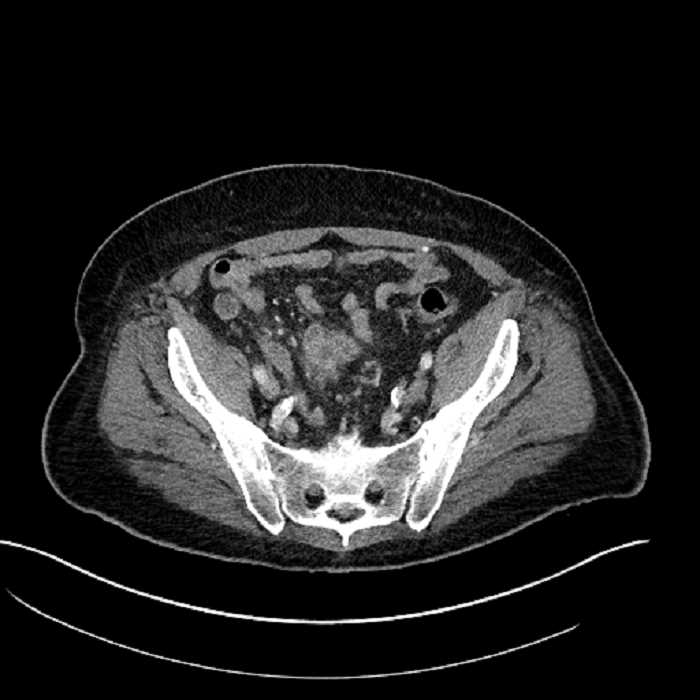

Age: 63

Sex: Male

Indication: Abdominal pain

• Mild mural thickening of a segment of the sigmoid colon with adjacent fat stranding and a 1.5 cm fluid and gas collection along the tip of an inflamed diverticulum

• Loss of the normal fat plane between this collection and adjacent loops of small bowel, which demonstrate mural thickening

• No bowel obstruction

Acute sigmoid diverticulitis complicated by a small contained perforation and a large abscess in the right hepatic lobe. Additional small subcapsular abscesses along the anterior margin of the left hepatic lobe.

Additionally, loss of the normal fat plane between the peridiverticular collection and adjacent thickened loops of small bowel raises the potential for an enterocolonic fistula.

Hepatic abscess showing the double target sign with low density internally surrounded by a thin inner enhancing rim (red arrow) and ill-defined outer low density rim (yellow arrow). Blue arrow indicates an internal septation. Red arrows: additional smaller subcapsular abscesses. Red arrow: focal contained perforation associated with diverticulitis.